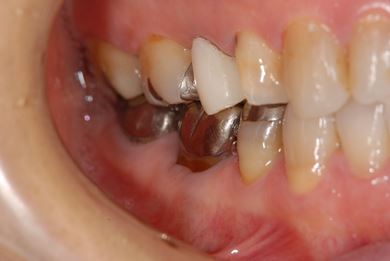

| 主訴 | 痛む歯を治療し、セラミックの歯にしたい。 | ||||||||||||||||||||||||||||||||

| 治療内容 | メタルボンドセラミック2本(メタルボンドセラミッククラウン用の土台2本)、ハイブリッドセラミックインレー2本 | ||||||||||||||||||||||||||||||||